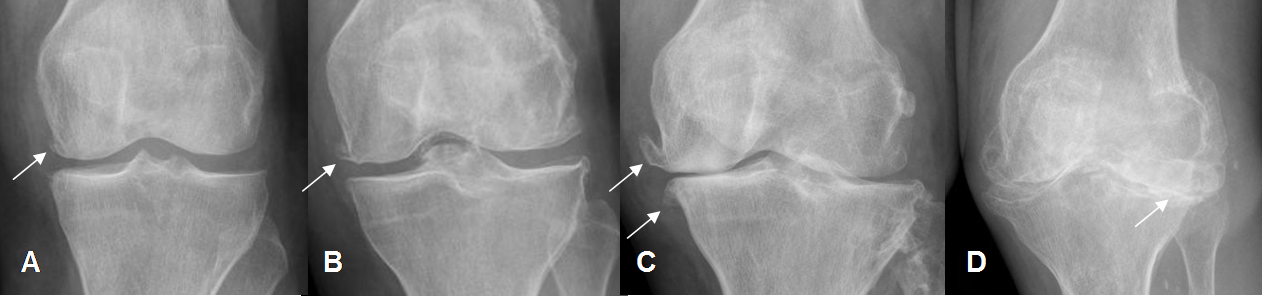

Se ha utilizado la escala de Kellgren-Lawrence (KL) para valorar la osteoartritis, con Rx simple: (42). (Fig 202).

Fig 202. Escala de la osteoartritis.

A: Rx AP. Estado 1: Incipiente formación de osteofito, en el cóndilo femoral medial.

B: Rx AP. Estado 2: Osteofito femoral, con leve disminución del espacio femorotibial.

C: Rx AP. Estado 3: Osteofitos con pérdida del espacio femorotibial.

D: Rx AP. Estado 4: Osteofitos con pérdida del espacio y esclerosis asociada.